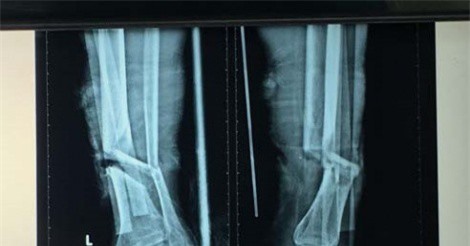

Cụ ông đi cắt cỏ thì không may bị máy cắt vào cẳng chân trái. Bệnh nhân nhập viện trong tình trạng bị đứt gần lìa 1/3 dưới cẳng chân trái.